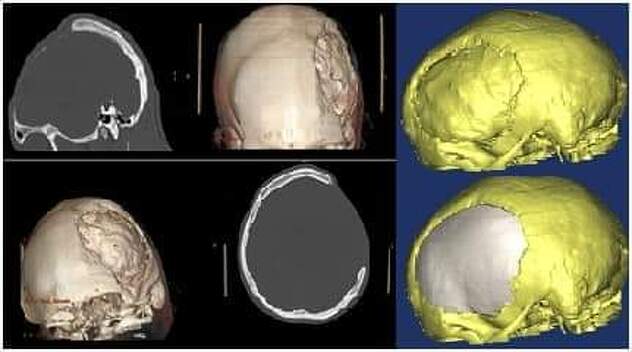

Ponovno se pokazalo da tehnologija i medicina idu rame uz rame. Na osnovu 3D kompjuterizirane tomografije glave napravljen je 3D model lobanje pacijenta, koji je poslužio za formiranje originalnog transplantata. Kalup za transplantat je napravljen na 3D printeru i milimetarski je odgovarao defektu kojeg je trebalo zatvoriti. Sama rekonstrukcija je uspješno realizirana i dobijen je maksimalan estetski i funkcionalni rezultat.

“U odnosu na ranije rekonstrukcije ova je bila mnogo kompleksnija i tehnički najzahtjevnija, posebno zbog rekonstrukcije bazalnog i prednjeg dijela lobanje, što samo po sebi, značajno produžava trajanje operacije. Posebno ističemo da je sama metoda inovativna i u cijelosti je, u jako skromnim materijalnim uslovima, uvedena i realizirana u Zenici”, poručili su iz zeničke bolnice.